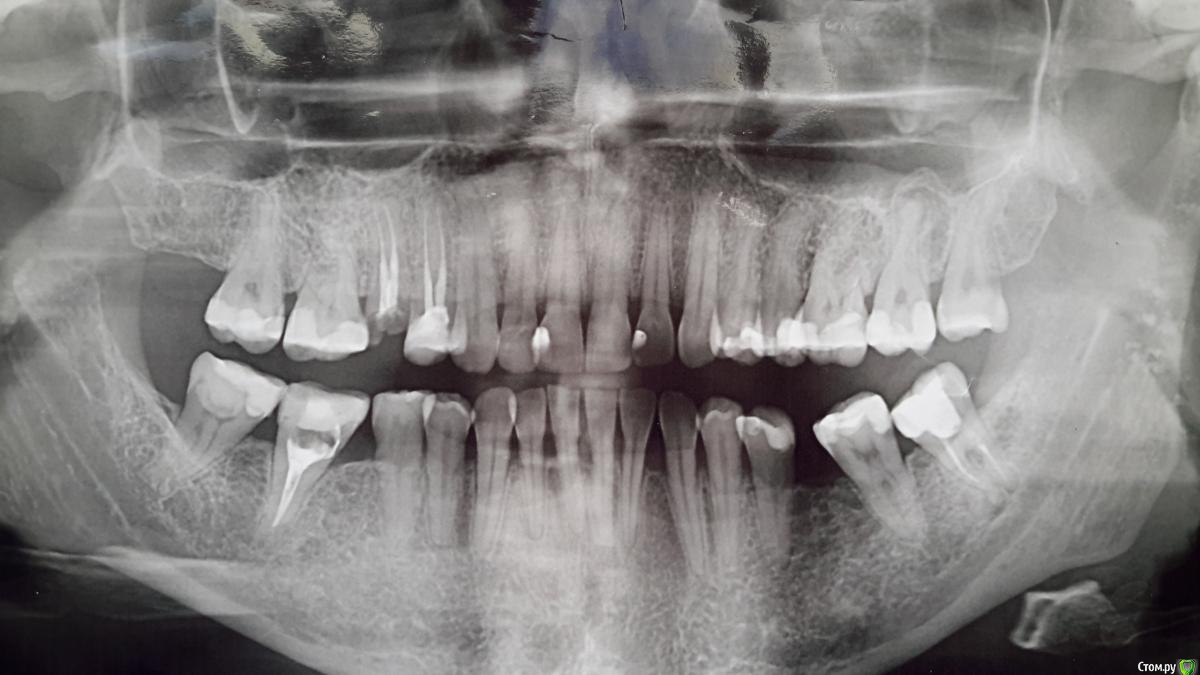

velena37 Опубликовано 14 марта, 2020 Поделиться Опубликовано 14 марта, 2020 Доброе время суток всем! Пару дней назад стоматолог на приеме сказал, что видит на снимке кисту. Хотелось бы услышать мнение уважаемых специалистов. Видите ли кисту вы? Ссылка на комментарий

dok1 Опубликовано 14 марта, 2020 Поделиться Опубликовано 14 марта, 2020 Зуб номер 27 Ссылка на комментарий

Паращук Роман Опубликовано 15 марта, 2020 Поделиться Опубликовано 15 марта, 2020 Спасибо Вам!!Если Вы знаете об этом, расскажите, пожалуйста, перспективы лечения? Она большая? А почему не темная и зуб не депульпирован?Перспективы отличные. По статистике около 80% успеха лечения. Не большая. Зуб не депульпирован,так как пульпа зуба погибла после установки пломбы и продукты распада с инфекцией "выходят за корень". Ссылка на комментарий

red_butler Опубликовано 15 марта, 2020 Поделиться Опубликовано 15 марта, 2020 А можно еще вопрос? Киста это то, что синим или то, что красным?Синим, но это не киста а периодонтит Ссылка на комментарий

dentikl Опубликовано 15 марта, 2020 Поделиться Опубликовано 15 марта, 2020 типа не сделал снимок до лечения кариеса, и не диагностировал периодонтит, который бывает и без вскрытия полости зуба1.Тут весь рот в глубоких кариесах(хронических пульпитах).2.Может быть на 27 есть патология,а может и нет.3.До лечения кариеса нужно делать снимок? Ссылка на комментарий